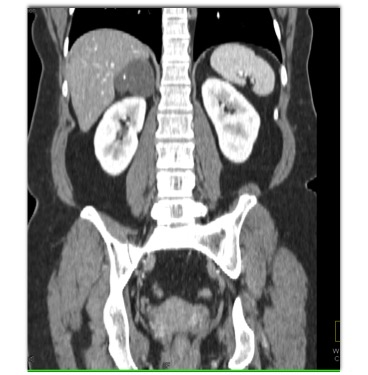

The most likely diagnosis for the right adrenal mass is?

adrenal cyst

adrenal hematoma

adrenal lymphangioma

adrenal carcinoma